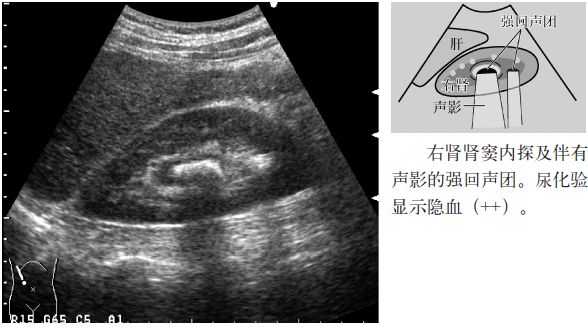

图2 肾结石

注意:小于5mm的肾结石几乎无声影,但是,超声入射角度微妙的变化可以显示点状高回声和声影。因此,平静呼吸时或改变经肋间扫查的位置,有时会出现声影,因此,不仅要在吸气时观察,还应在呼气时或改变经肋间扫查的位置时进行观察。